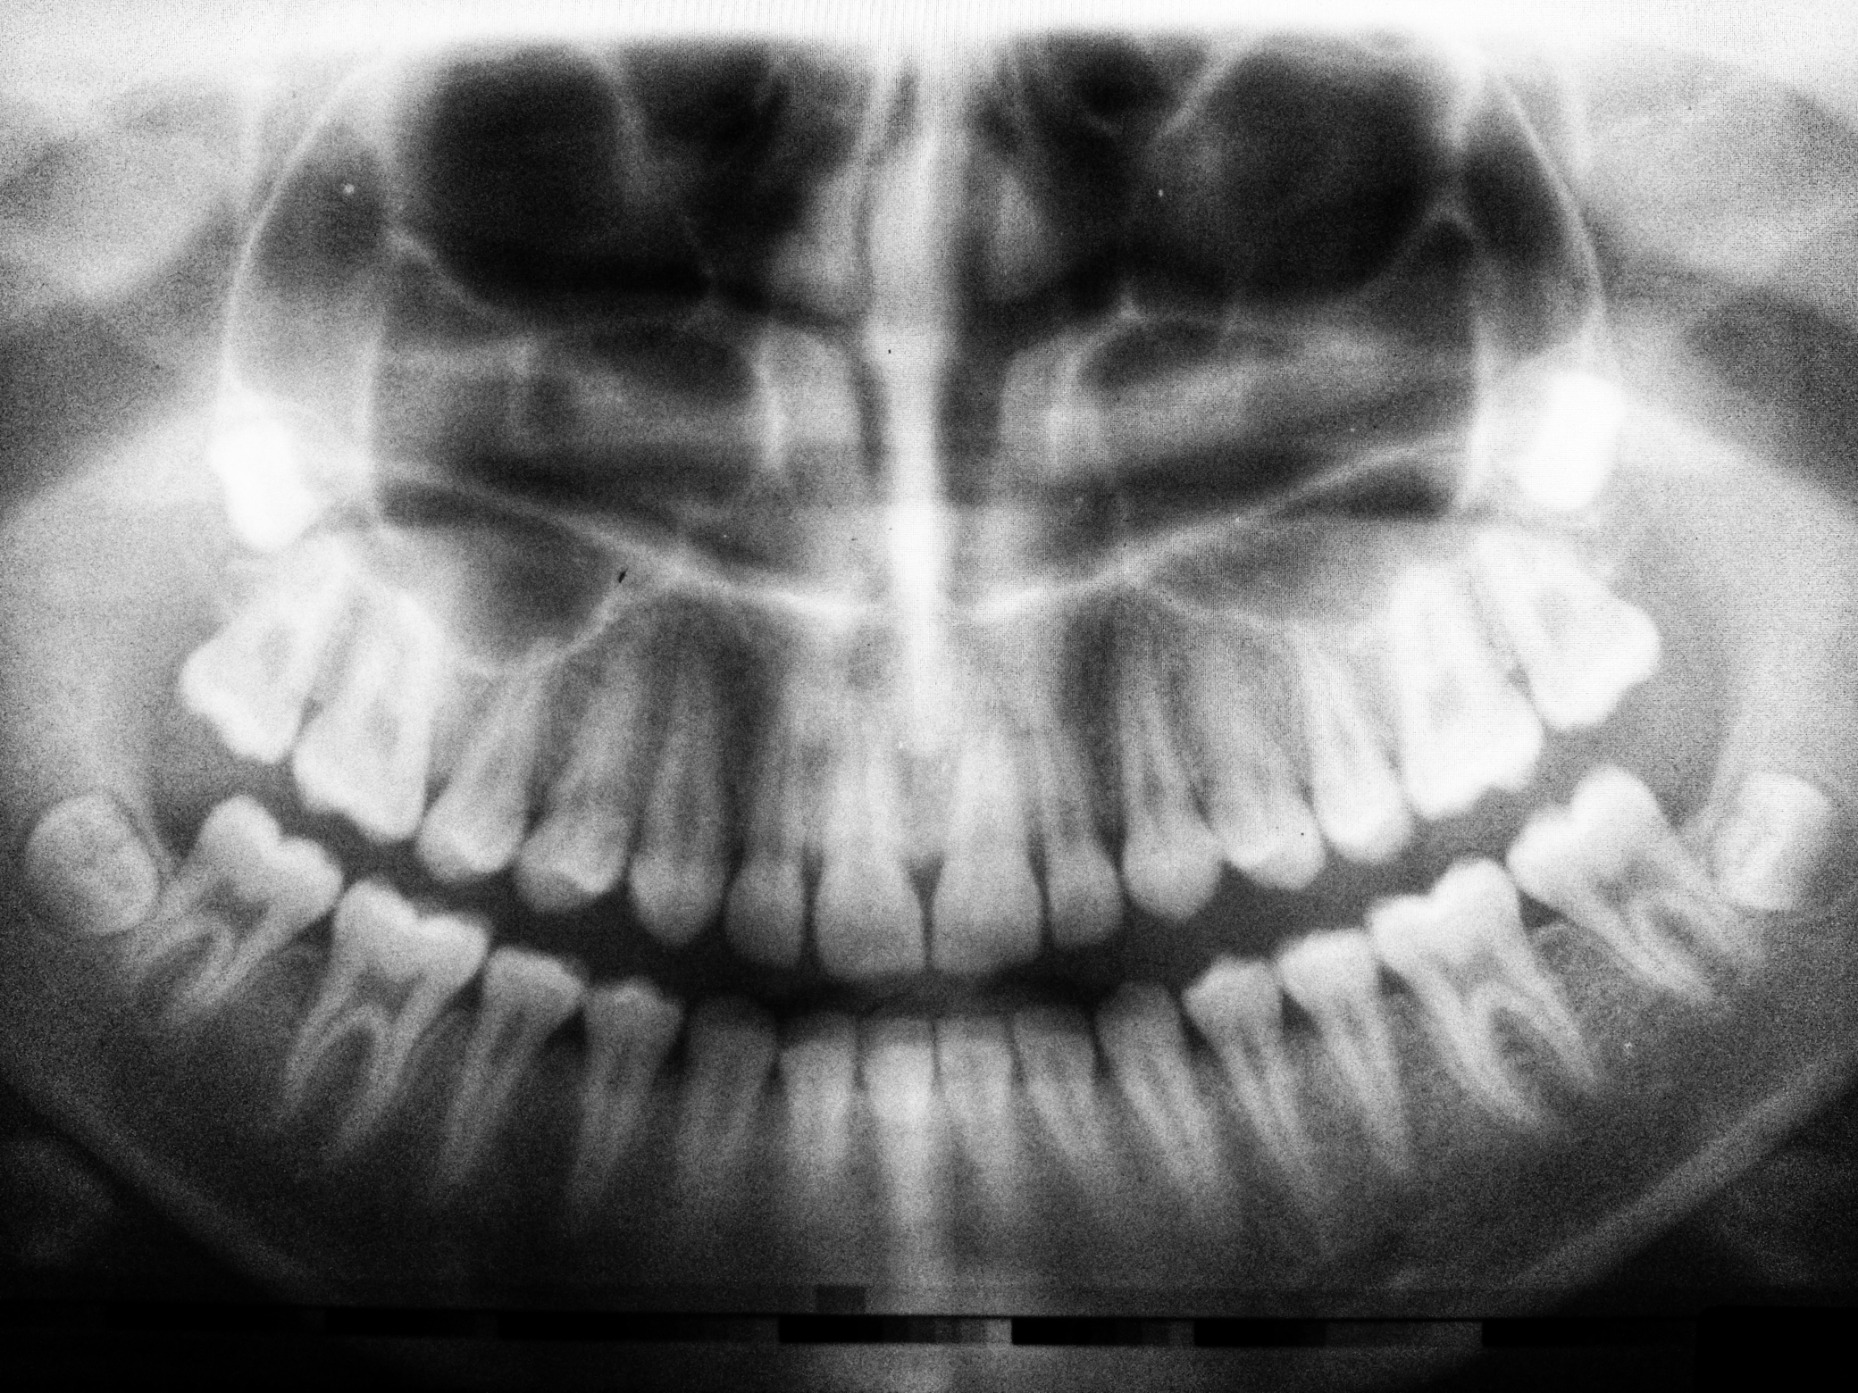

The pulp inside your tooth can become infected due to deep decay, repeated dental procedures on the tooth, or a crack or chip in the tooth. Symptoms of pulp infection include pain, prolonged sensitivity to heat or cold, discoloration of the tooth, and swelling and tenderness in the nearby gums. If left untreated, this infection can cause abscesses, leading to more severe health issues. A root canal may be necessary to remove the infection, “save” the tooth, and preserve its function.

The Root Canal Process

A root canal treatment is relatively straightforward, and with the expertise of our dentists at Integrity Dental Group, as comfortable as a routine filling. You can expect the following as part of your root canal therapy: